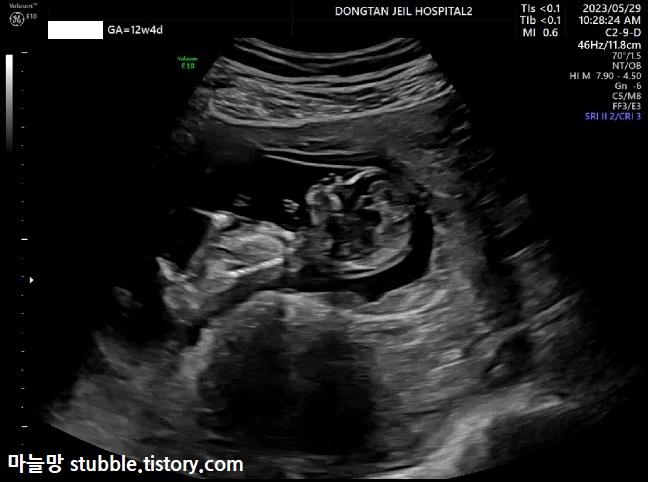

그리하여 혼자 들어가 누워서 초음파를 보게 되었어요. 이제는 산부인과에서 질초음파가 아닌 배초음파로 봅니다.

아기가 잘 움직인다고 초음파 쌤께서 말씀하셨어요.

안 본 사이에 아기는 사람의 형태가 되어 있었어요.

이쪽으로 돌았다가 저쪽으로 돌았다가 제가 봐도 아기가 잘 움직였어요.

초음파를 보는 시간도 생각보다 빨리 끝났고요. 5~6분 정도 봤어요.

그럼 오늘 본 초음파중에 하이라이트만 정리해 볼게요.

이번 초음파 사진은 병원 갈 때마다 항상 재보는 CRL이에요.

아기의 머리부터 엉덩이뼈 끝까지의 길이입니다. 우리 아기는 12주 4일 차 6.37cm입니다.

주수대비 계속 이틀이 느렸는데 이틀이 빨라졌어요. 아마도 초음파 쌤께서 아기 CRL 잴 때 아기를 반듯하게 쭈욱 펴서 재니깐 좀 더 키가 크게 나올 수 있었던 것 같아요.